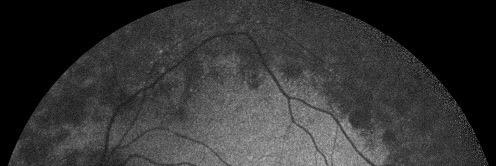

I’ll never tire of seeing THAT face - and while John is sadly no longer with us, the amazing work by @RetinaUK the pic was taken in aid of goes on and still needs your support. Please consider a festive donation to help save people’s sight. retinauk.org.uk #RP